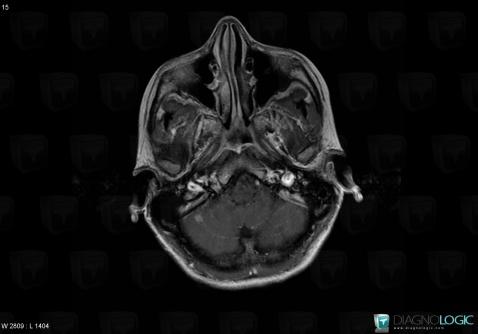

Toxoplasmosis, Posterior fossa, MRI

Here is the specific information in the key image above:

- Diagnosis Toxoplasmosis (link to Abscess), Location(s) Posterior fossa, with gamuts Infratentorial T2W or FLAIR hyperintense lesion